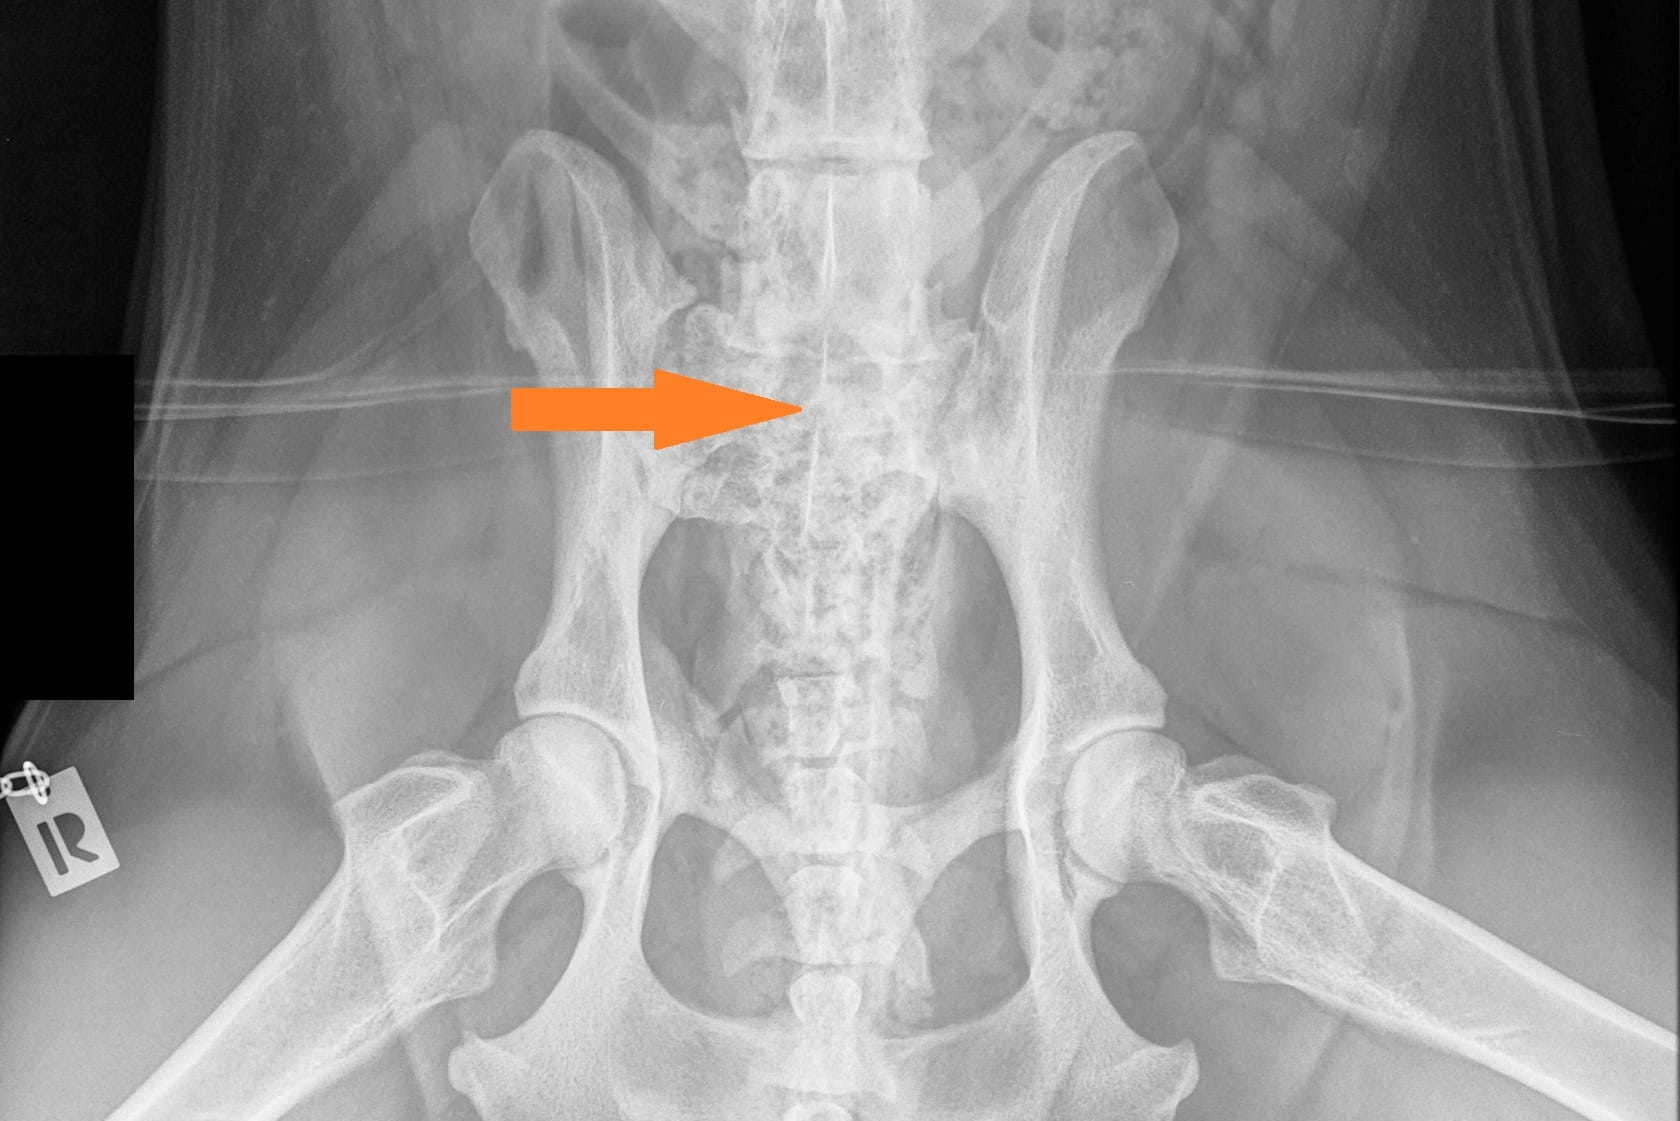

LTV3; asymmetrical; on the right in the VD photo the left side of S1 is shaped like a sacral vertebra and on the right side S1 is shaped like a lumbar vertebra including the spinous process.

The asymmetrical form, LTV3, seems to be a bit more tricky than the other forms. In some cases asymmetrical form comes with rotated pelvis, which might lead to unilateral development in hips. This is actually very logical; when the pelvis is not straight and in balance there will be uneven bear of weight between hips. In long term this uneven state might cause the worse hip wear sooner than the better hip and lameness and osteoarthritis may occur.

In the Finnish Kennel Club’s database 38,9% of Rhodesian Ridgebacks with LTV3 have one hip scored 1-2 degrees lower than the other one, ie. A/C (Oct 2020). The score doesn’t tell if the dog’s pelvis is straight or rotated.

“Asymmetrical LTV favours pelvic rotation over its long axis, resulting in inadequate femoral head coverage by the acetabulum on one side. Inadequate coverage of the femoral head favours subluxation, malformation of the hip joint, and secondary osteoarthritis. Asymmetrical hip conformation may therefore be the sequela of a LTV and mask or aggravate genetically induced canine hip dysplasia.”

(Flückiger M., Frank Steffen F. et al 2017)